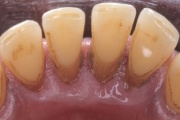

Krooniline parodontiit

Krooniline parodontiit on mikroobide poolt põhjustatud hammaste tugikudede põletik, mille tulemusena tekib progresseeruv alveolaarluu (nähtav röntgenograamil) ja periodontaalligamendi destruktsioon, igemetaskute moodustumine, igeme retsessioon või mõlemad kahjustused kombineeritult. Loe edasi »

- igemed veritsevad (19)

- igemed punetavad (21)

- ige on paistes (mädapunn)

- igemed on tursunud/vohavad (17)

- igemepiir on taandunud (3)